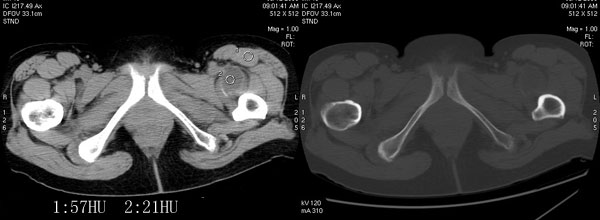

以下是引用jiajie在2006-7-14 17:19:00的发言:[br]ct所见:双侧髋关节不对称,左侧关节间隙变窄,关节面毛糙。左侧股骨头变形、无明显变小,前上缘与髋臼融合,融合处骨质明显增生硬化,并见数个小囊变影。股骨头下端与股骨颈交界部见囊样变,邻近肌肉内见囊样密度减低区,ct值24hu。右侧髋关节形态未见异常。[br][br]ct诊断:左侧髋关节结核可能,请结合临床资料进一步分析。

以下是引用lihuuuu在2006-12-5 10:14:00的发言:[br]定位像示:左侧髋臼变浅,倾斜度加大,髋臼外上缘呈波浪状不规则,骨质增生硬化,髋关节上缘间隙明显变窄,股骨头向外上轻度移位。轴位像示:左侧股骨头变形,前上缘与髋臼融合,融合处骨质明显增生硬化,并见数个小囊变影。股骨头下端与股骨颈交界部见囊样变,邻近肌肉内见密度减低区,ct值24hu,内缘见弧形高密度钙化影。右侧髋关节形态未见异常。[br]ct诊断:左侧髋臼发育不良[br] 左侧股骨头缺血性坏死[br] 左侧肌肉内低密度影伴有高密度钙化-考虑早期骨化性肌炎[br] [br]“我认为在描述上已经写了肌肉部分,印象诊断里应该写主见”[br]